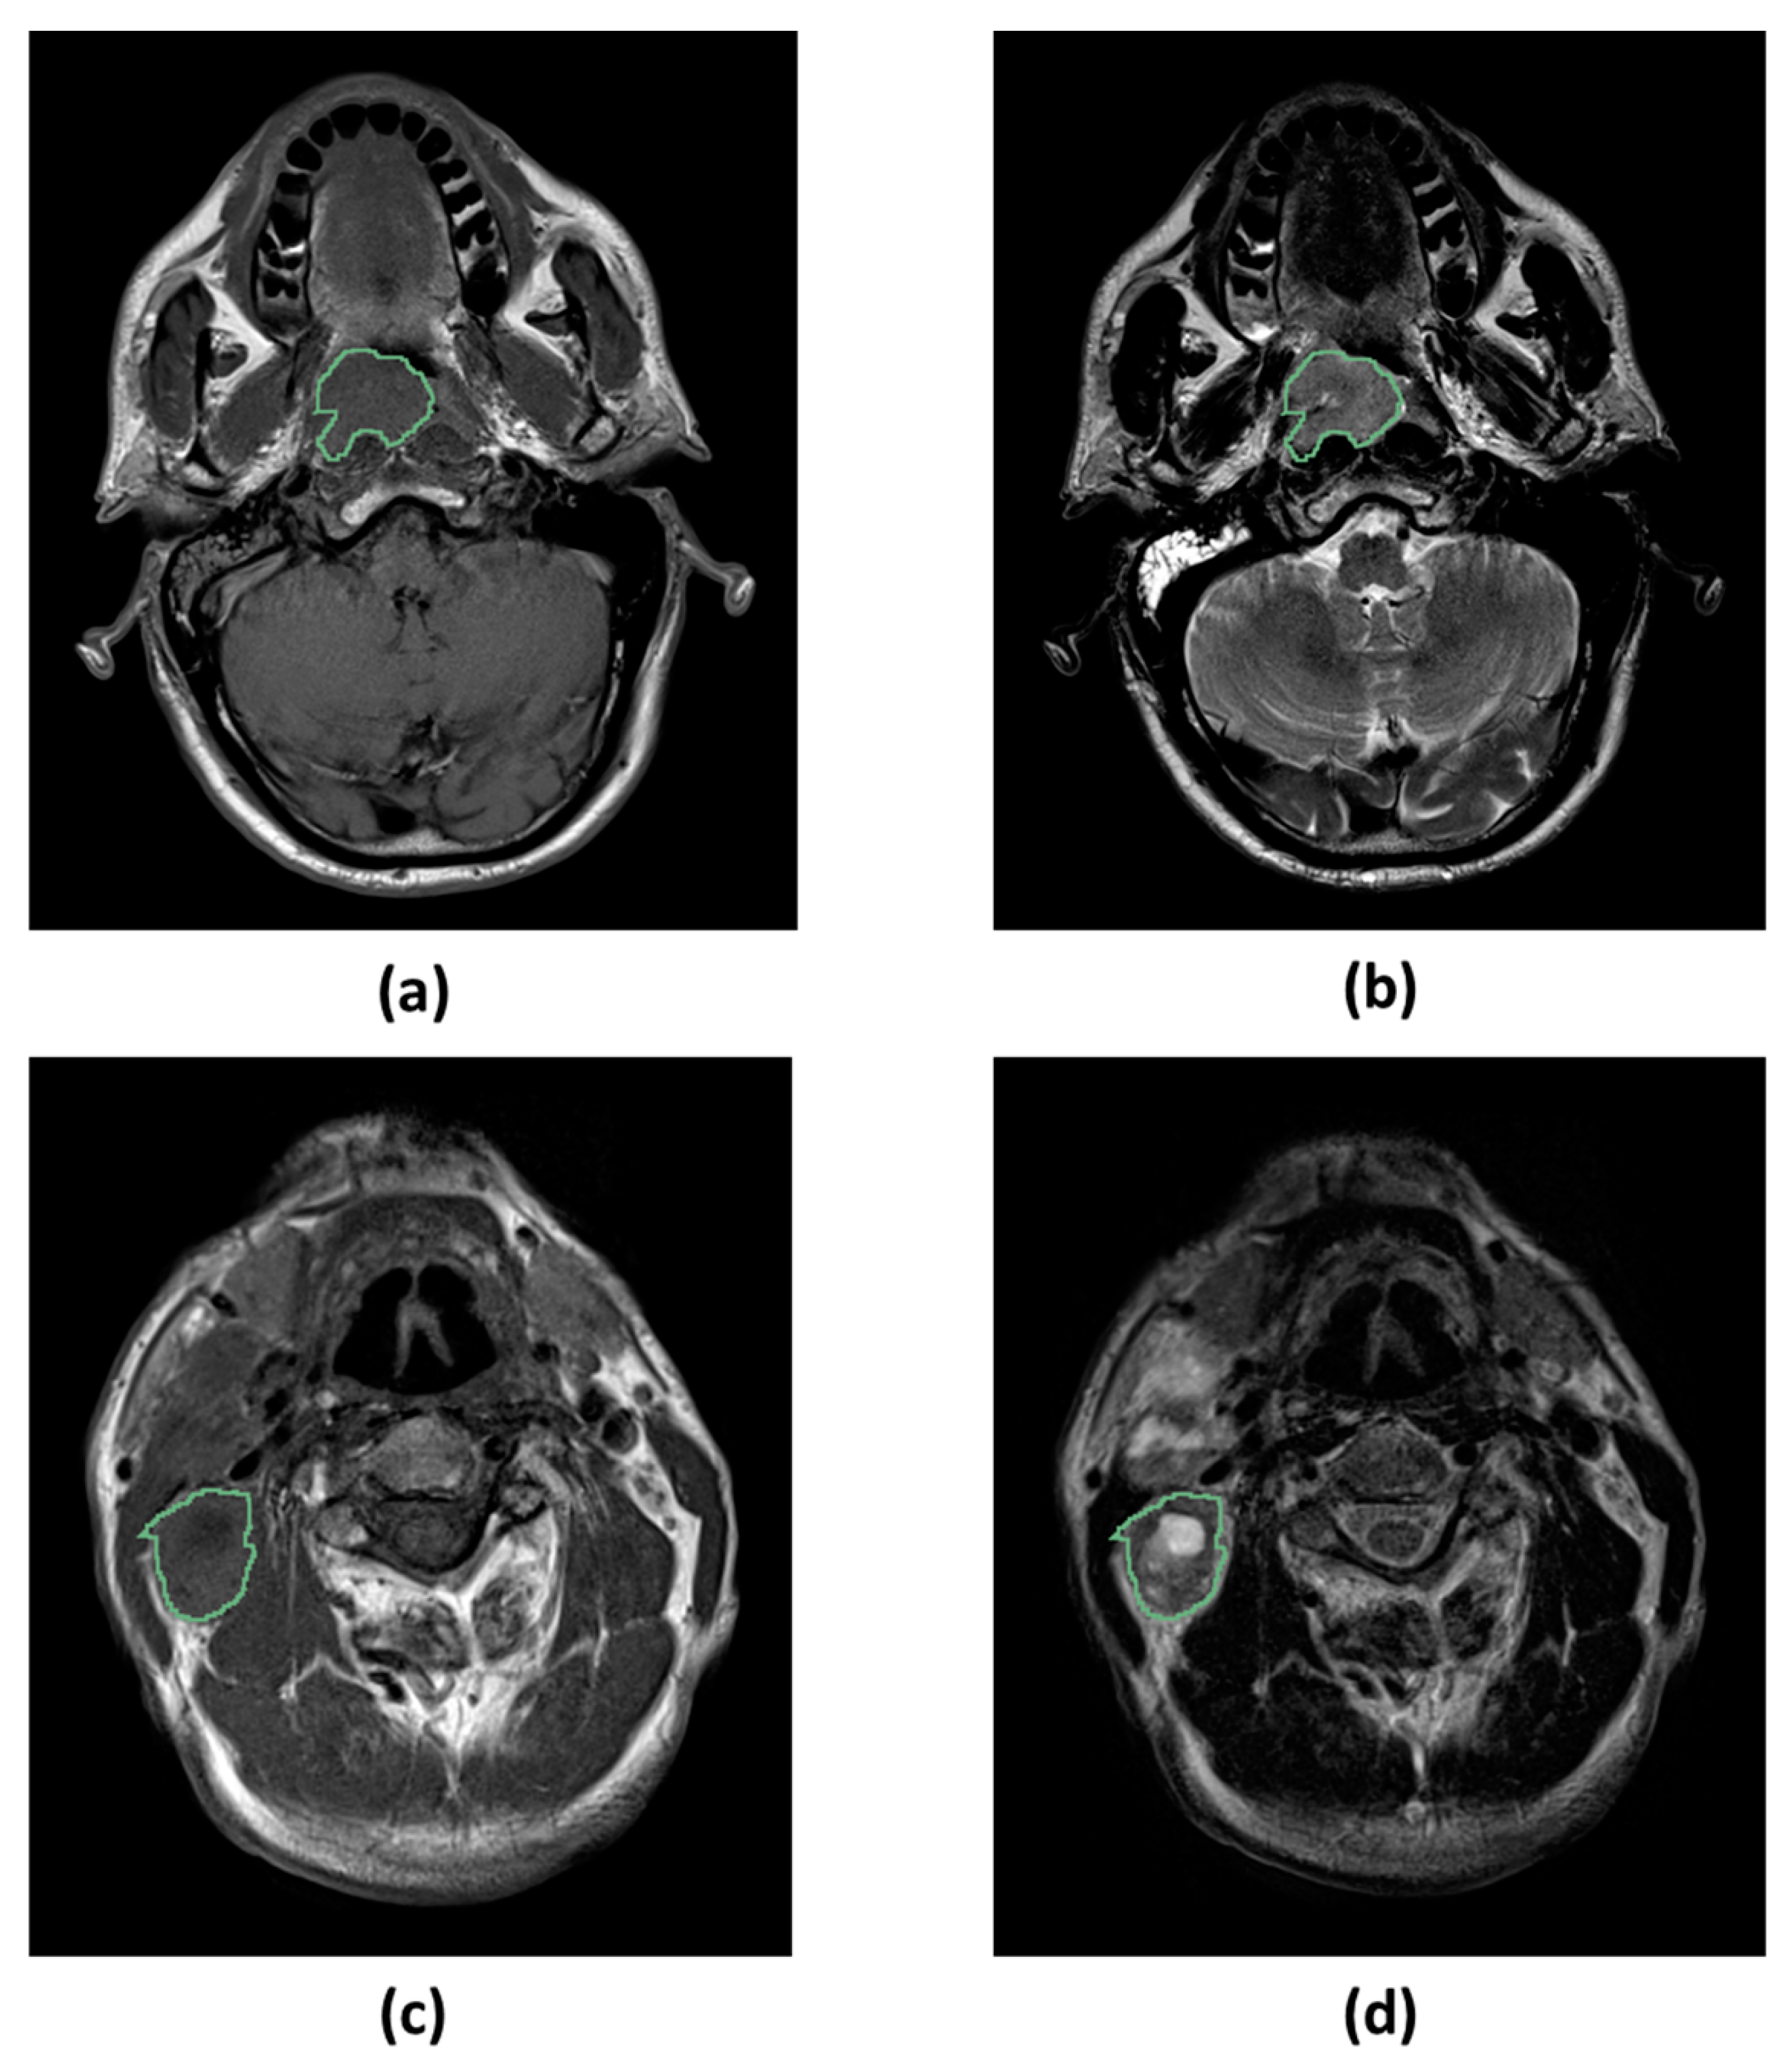

4.5. Image Segmentation